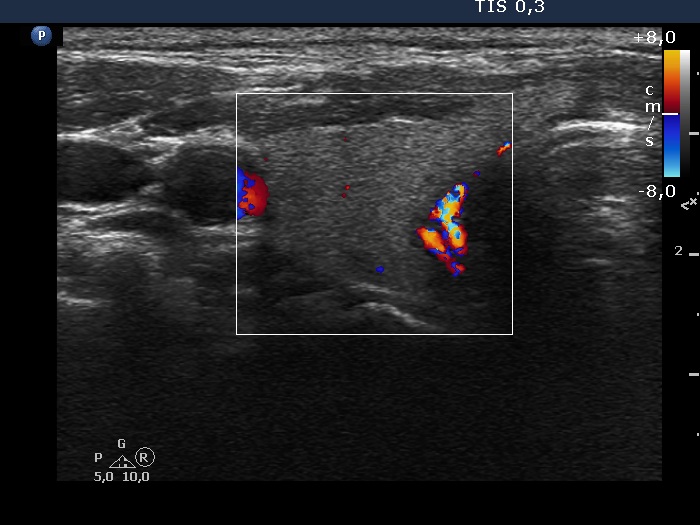

Second examination a year later (second row of images)

Clinical data: The patient had no complaints except for COVID-19 infection 3 months before the present visit.

Palpation: unchanged.

Hormonal investigation: TSH 3.10 mIU/L.

Ultrasonography revealed that the discrete hypoechoic lesion in the left lobe had increased in size, the dimensions were 4x4x5 mm, width, depth and length, respectively. There was a lymph node lateral to the left lobe. The node presented a heterogeneous pattern and lacked a regular hilum.Suggestion: repeat ultrasound in 3 to 6 months.